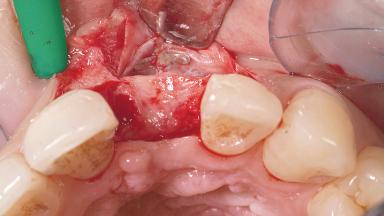

Late Placement of an Implant in a Maxillary Left Central Incisor Site

A 30-year-old female patient had lost tooth 21 and was referred to our clinic for consultation and treatment. Due to advanced apical infection, tooth 21 had been extracted two months earlier at another clinic and an acrylic-resin tooth had been bonded to the adjacent teeth. The patient desired implant treatment to avoid any damage to the adjacent natural teeth. While the patient had no history of any systemic disorder, she was a heavy smoker and exhibited medium to advanced periodontitis in the entire jaw. After the initial treatment to achieve a pocket probing depth of less than 4 mm and no bleeding on probing, a decrease in the height of the papillae mesial and distal to the extraction site and overall gingival recession were observed.

Bone Augmentation Horizontal|Staged

Augmentation Materials Autogenous chips|Membrane

Soft Tissue Grafting Simultaneous

Bone Volume Deficient horizontally, requiring prior grafting